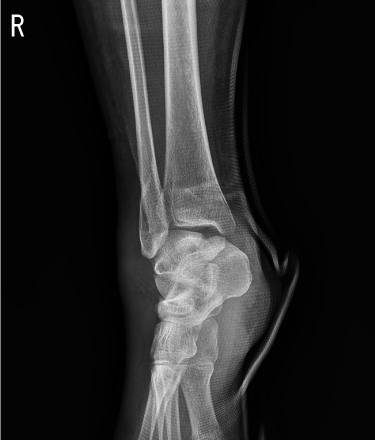

원위 상완골 골절

2022.07.14

2023.02.07